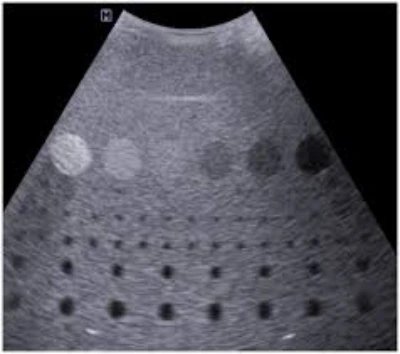

Com atuação consolidada desde 2014, a ULTRASSOMCENTER é especialista na locação e manutenção de equipamentos de ultrassom, oferecendo soluções completas para o setor médico.

Localizada em Santo André (SP), a empresa atende São Paulo Capital, Grande São Paulo, interior e Sul de Minas Gerais, assegurando excelência técnica e atendimento diferenciado.

A ULTRASSOMCENTER disponibiliza equipamentos de marcas reconhecidas, prontos para uso imediato, com instalação, suporte técnico e manutenção preventiva.